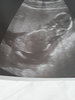

Super :) a wiesz ile ma cm? Jakies zdjecie?? ❤

Zdjęcie dzis dostałam mało jakieś widoczne, mierzy 9,8cm :happy:

15451369633962996762342897956401.jpg

• 15451369633962996762342897956401.jpg

1 020,9 KB · Wyświetleń: 326